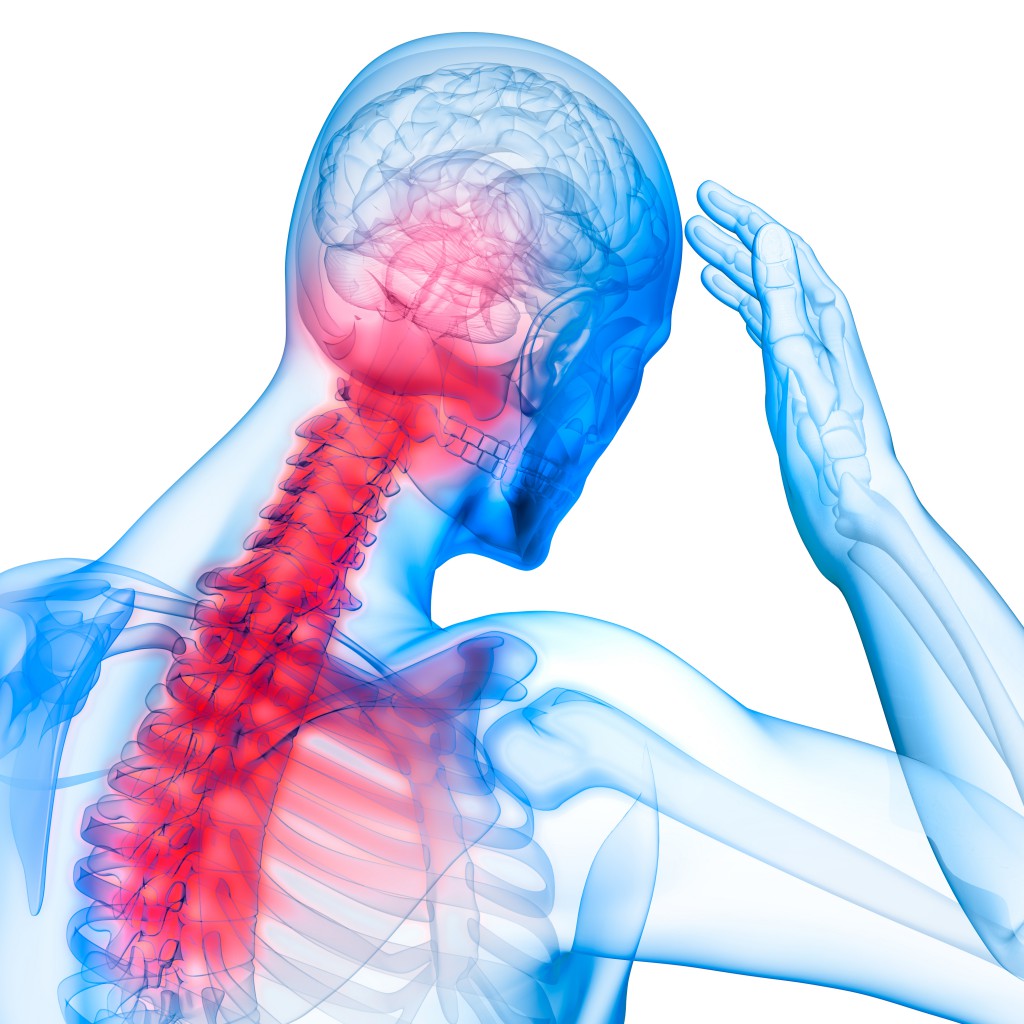

HWS Syndrom – Ursachen | Symptome | Behandlungen

HWS-Blockade lösen Übungen für die Halswirbelsäule + Video

Bandscheiben-Forum > HWS Schmerzen seit Wochen

HWS-Syndrom: Symptome und Behandlung

HWS Beschwerden seit 3 Jahren? (Befund)

Chirotherapie – Manuelle Medizin in der HNO Praxis Dr. Axel Suhrborg …